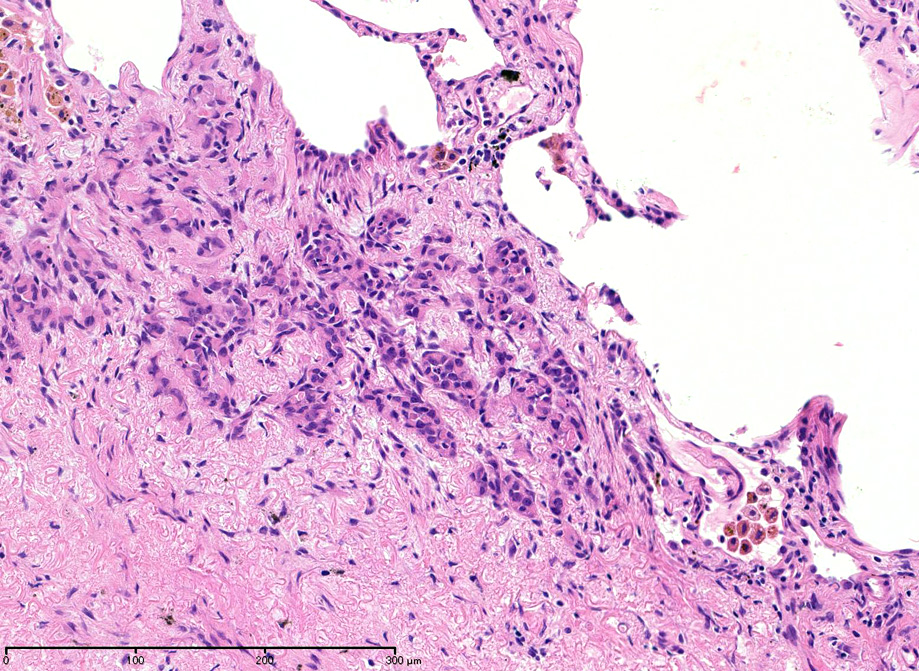

直径5-6mmの, 中央に弾性線維をふくむfibrous noduleがあり, 腫瘍細胞は結節の辺縁部に沿って認められる。

クリックすると大きな画像が見られます。